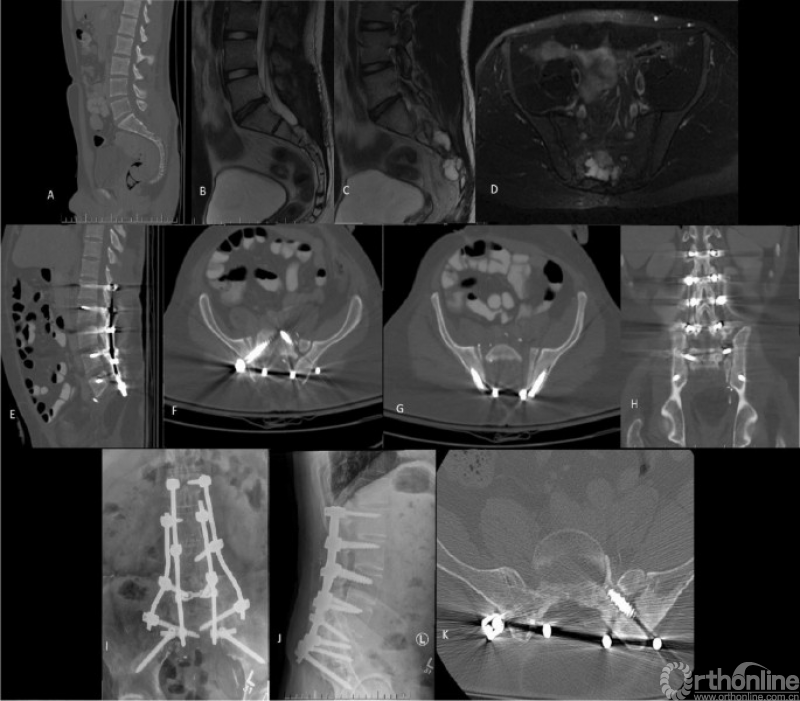

Ahmed Cherry等人发表的《Lumbopelvic shortening and local host bone-to-host bone reconstruction:a surgical method for lumbopelvic fusion following total sacrectomy》描述了全骶骨切除术后腰骶融合重建技术,用于治疗全骶骨切除术后的大骶骨缺损。